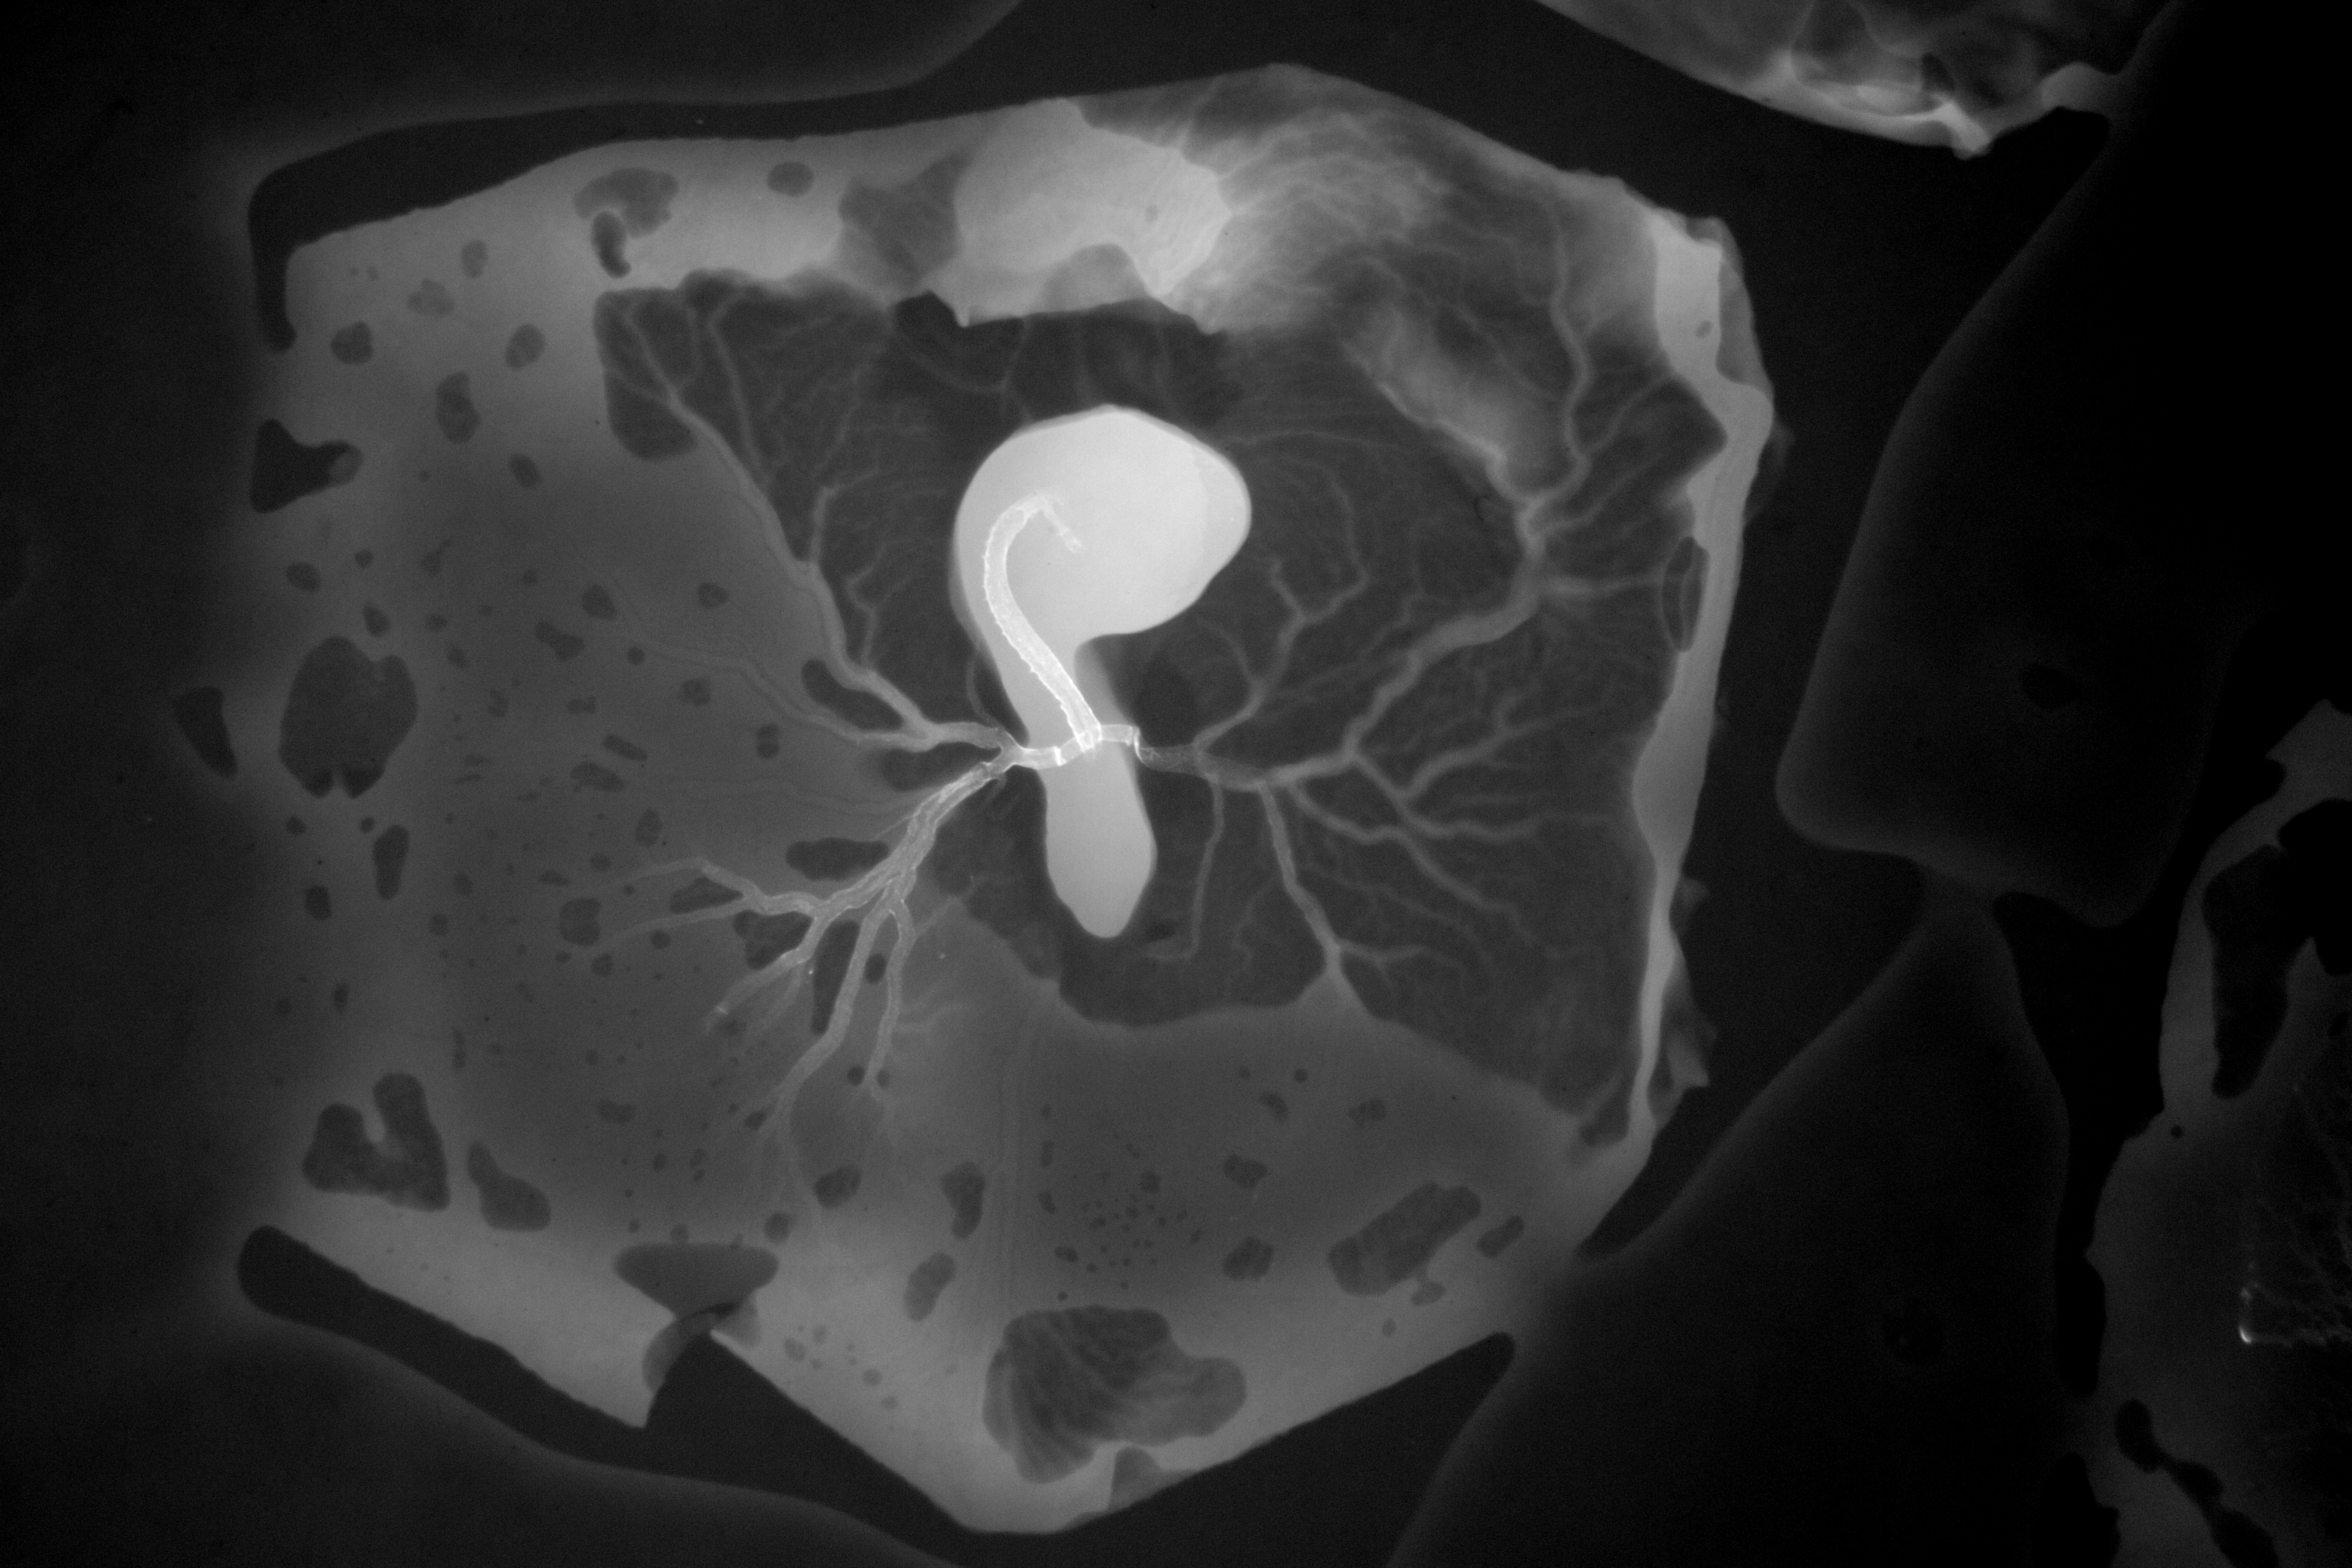

Chick Embryo Microangiography

Hamburger-Hamilton (HH) Stage 16 (approx. 2.1 - 2.5 days)

X-Ray Micrographs